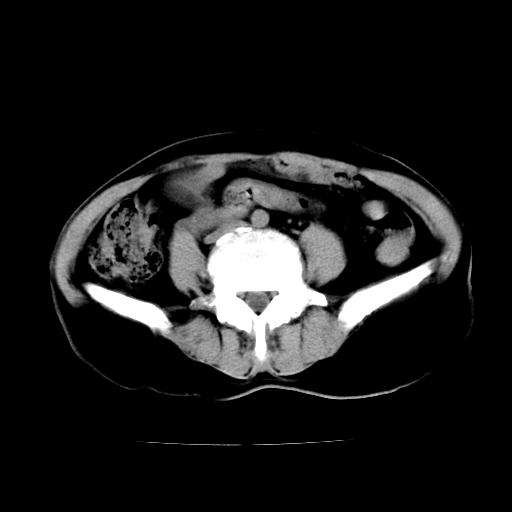

标题: CT24785:女,62岁,发现下腹部肿物半年。 [打印本页]

女,62岁,发现下腹部肿物半年,下腹部不适。

考虑肠系膜间质肉瘤或脐尿管癌可能性大。

考虑回肠间质瘤,不排除卵巢癌可能。